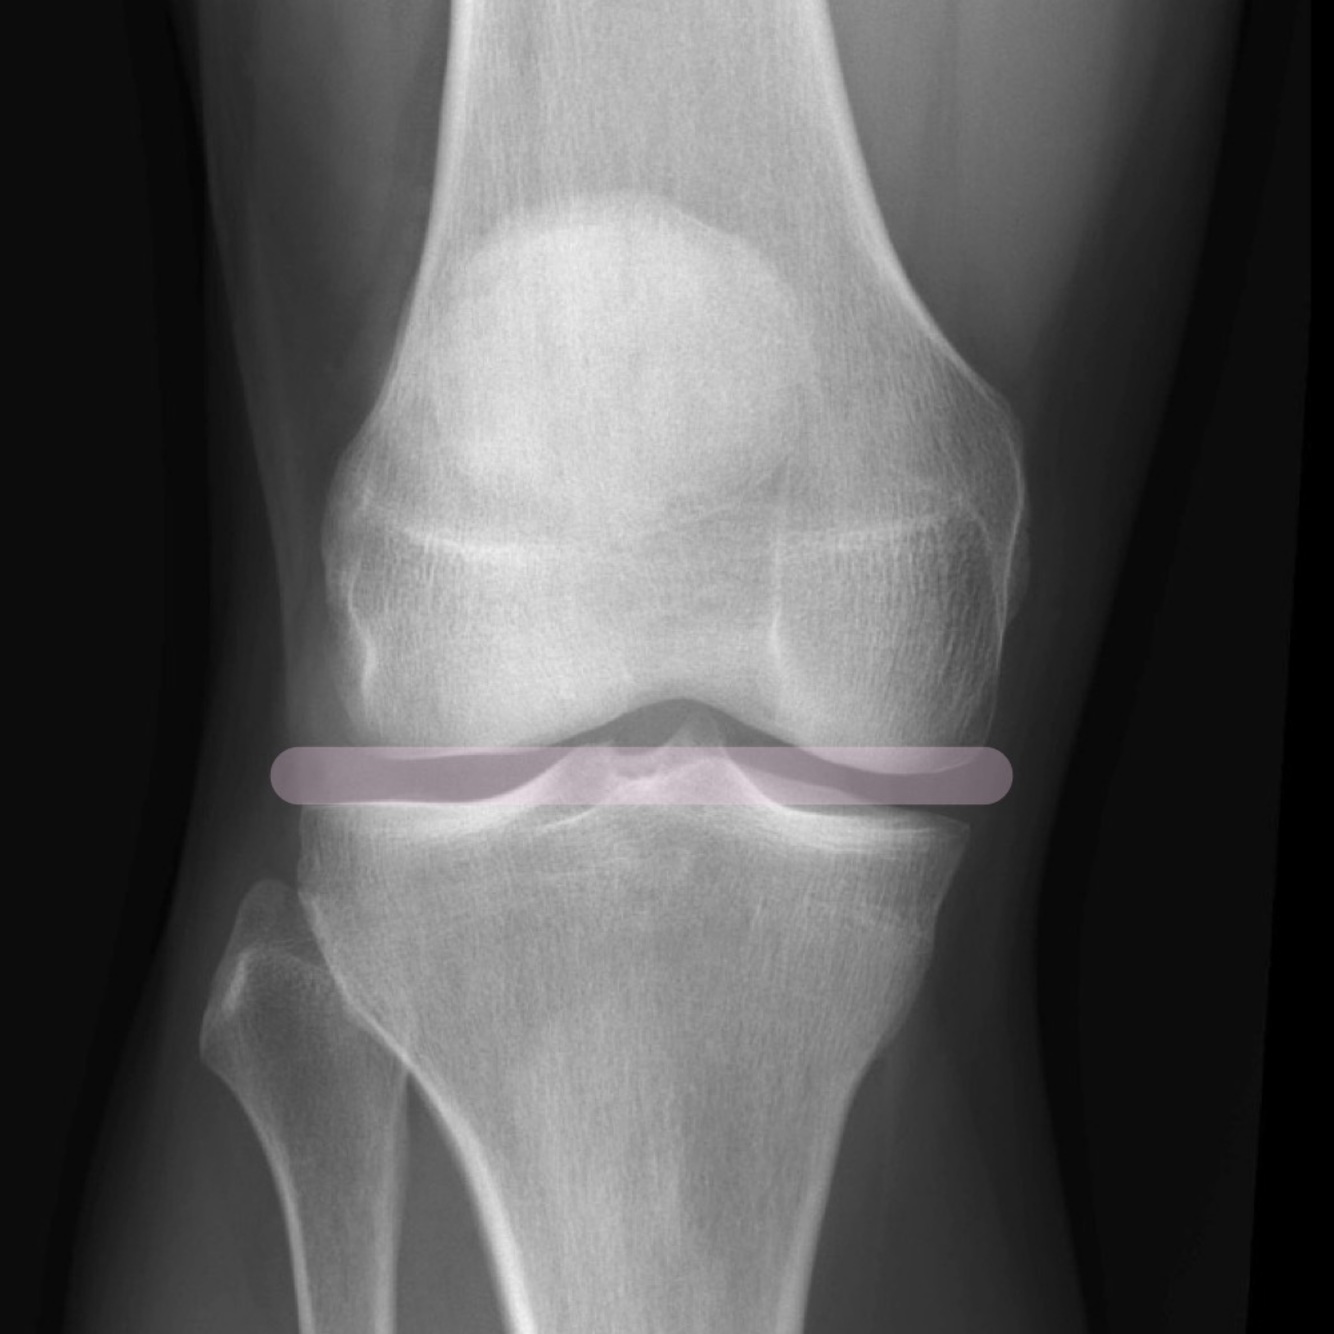

Qu’est-ce que je vois dans ma projection AP du genou

• La patella est surimposée au fémur

• Les espaces des compartiments interne et externe fémoro-tibiaux

sont égaux

• Léger valgus physiologique

• La tête fibulaire est surimposée au

tibia